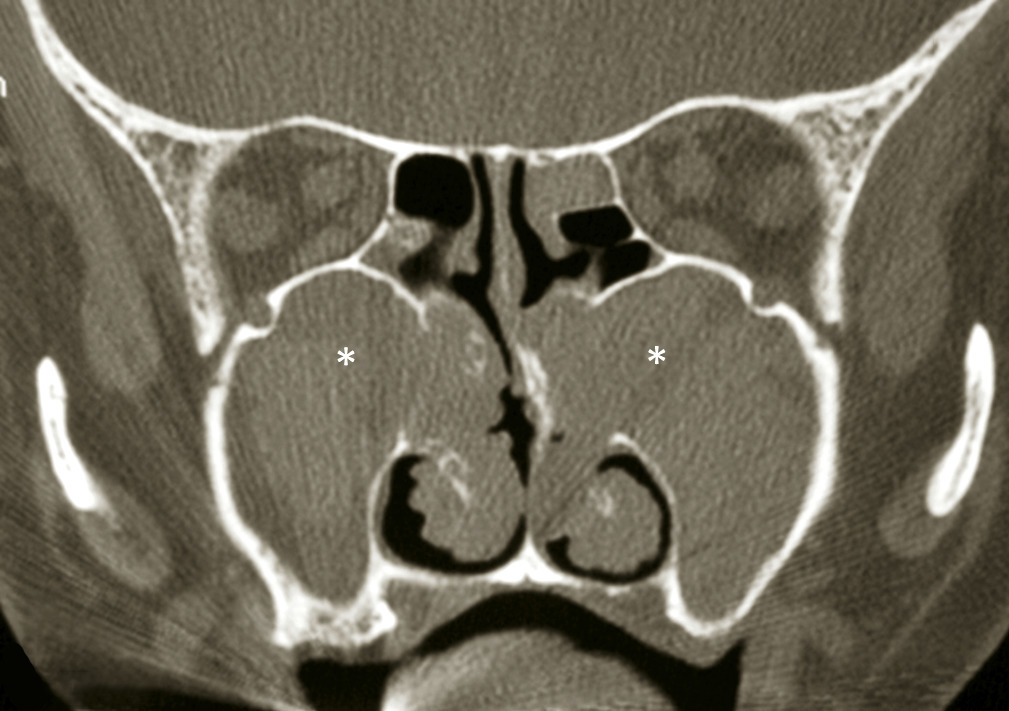

Le bilan clinique est complété par une tomodensitométrie qui montre des opacités sinusiennes plus ou moins diffuses. Une des particularités des patients suivis pour mucoviscidose est d’avoir des variations de pneumatisation des sinus (en particulier une hypoplasie des sinus frontaux) ou des distensions muqueuses des sinus maxillaires(fig. 2) avec refoulement médian des cornets inférieurs.4 En cas de céphalées persistantes, des complications à type de poches muqueuses ethmoïdo-frontales appelées mucocèles doivent être recherchées.

Le bilan clinique est complété par une tomodensitométrie qui montre des opacités sinusiennes plus ou moins diffuses. Une des particularités des patients suivis pour mucoviscidose est d’avoir des variations de pneumatisation des sinus (en particulier une hypoplasie des sinus frontaux) ou des distensions muqueuses des sinus maxillaires